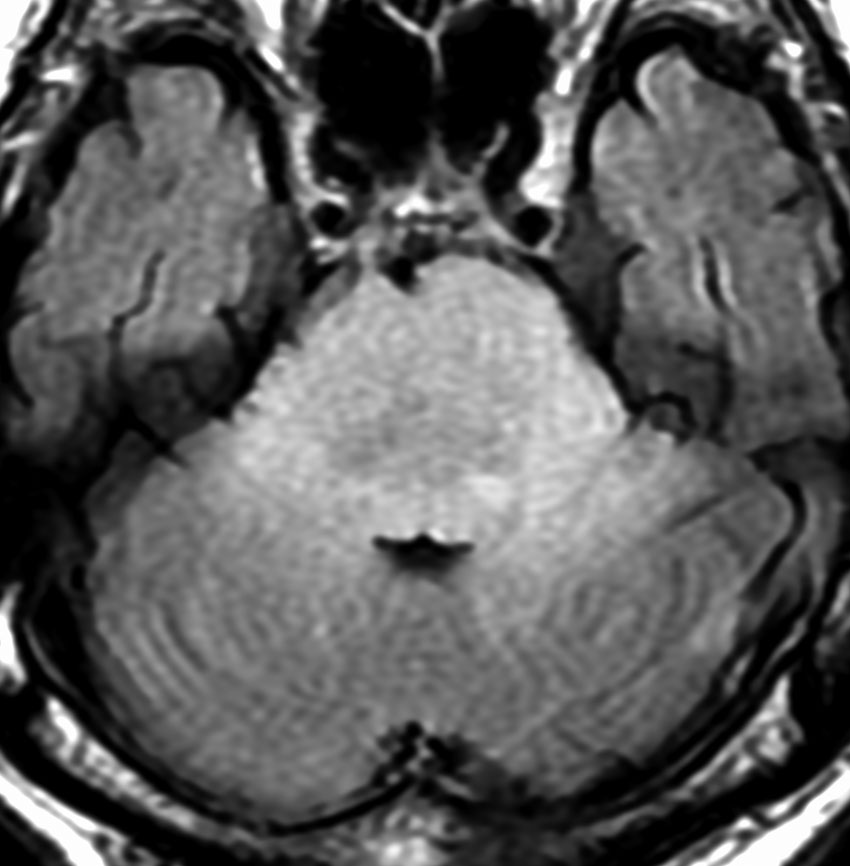

MRI画像所見 60代で嚥下障害と構音障害で発症した例

延髄から中脳まで腫瘍があって脳幹部が腫れています。この画像ですと,小児のびまん性橋膠腫(DIPG,びまん性正中グリオーマ)のように見えます

両側視床から大脳基底核,両側大脳半球深部白質,脳梁まで広範囲に腫瘍が存在します。退形成性星細胞腫のようにまだらにガドリニウム増強されます。